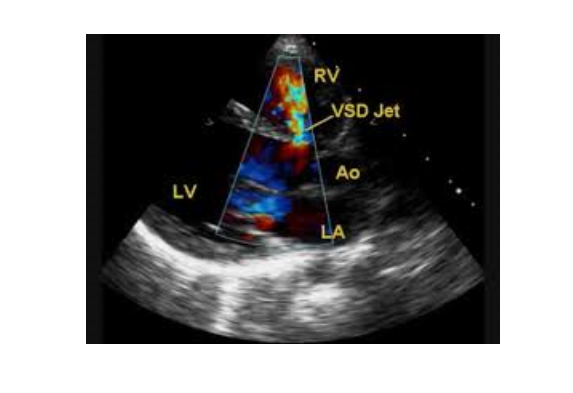

4. Siêu âm Doppler tim

Khi chùm tia siêu âm đi qua 1 vật thể chuyển động sẽ sinh ra hiệu ứng Doppler. Hiệu ứng Doppler là đại lượng phản ánh vận tốc của vật thể chuyển động được thu nhận, xử lý và biểu hiện qua dạng âm thanh, dạng sóng hoặc mã hóa thành màu. Trong siêu âm Doppler tim, hiệu ứng Doppler phản ánh vận tốc chuyển động của dòng máu và của cơ tim. Dòng máu đi qua chỗ hẹp có vận tốc lớn, khi đó tín hiệu âm thanh sẽ có âm lượng lớn và âm sắc cao, tín hiệu dạng sóng sẽ có biên độ lớn. Với Doppler mầu, dòng máu được mã hóa thành mầu đỏ nếu đi về phía đầu dò và thành mầu xanh khi đi xa đầu dò, theo đó sẽ phát hiện được các dòng máu bất thường trong tim. Nói một cách ngắn gọn, siêu âm Doppler tim là phương tiện rất hữu hiệu trong đánh giá huyết động qua các van tim, phát hiện các dòng máu bất thường trong tim và tình trạng vận động của cơ tim.